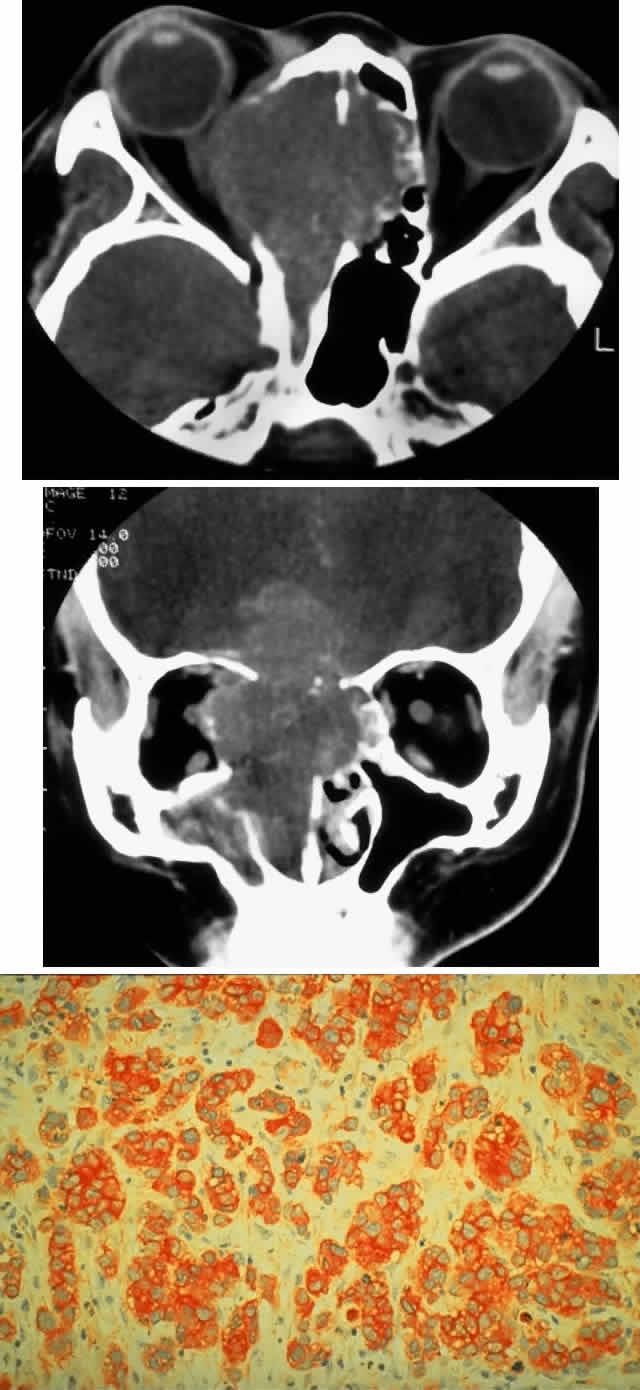

Extrascleral extension occurs in 10% to 15% of patients with uveal melanomas118–120 and may present clinically as a visible anterior nodule, as proptosis in patients with known intraocular tumor (Fig. 13), with phthisis and unsuspected tumor, or as a mass in orbital recurrence. Orbital recurrence associated with hepatic metastasis has been described as late as 42 years after primary enucleation.121 Orbital extension may only become evident at the time of surgery; however, the use of ultrasonography and CT scan may lead to increasing preoperative detection of extrascleral nodules.

Fig. 13. A 65-year-old man presented originally with a right retinal detachment and secondary glaucoma due to a large choroidal melanoma. The patient refused enucleation and self-treated instead with herbal medicines and “health foods.” He presented again 6 years later with acute onset of proptosis associated with pain, periocular edema, erythema, and marked restricted ductions (A). CT scan revealed the intraocular tumor, with massive orbital extension and displacement of the globe anteriorly, downward, and laterally (B and C). He underwent lid-splitting exenteration and split-thickness skin graft from the anterior thigh. The gross specimen shows the massive orbital component of melanoma, which had extended from the posterior choroid through emissarial vessels (D). An area of predominantly spindle-shaped melanoma cells with scattered, heavily pigmented macrophages is shown (E) (H & E, × 200). (D and E courtesy of Valerie A. White, MD, Department of Pathology, University of British Columbia, and the Vancouver Hospital and Health Sciences Center.)

The controversy over the management of orbital recurrence parallels that of intraocular melanoma. It does seem that by the time extrascleral and orbital extension is evident, other biologic factors are already in play that dominate the grave mortality rate, which is 73% to 81% in these circumstances.119,122 The role of exenteration has not yet been defined in a prospective controlled study but there is strong retrospective evidence suggesting that exenteration does not afford protection from metastases, except perhaps in cases of frank transection or nonencapsulation at enucleation.122 Shields and colleagues have summarized their current management (Table 9)123 based on the type of extrascleral extension (flat, nodular, vortex vein, or recurrence after enucleation) and the timing of detection (clinical examination, at surgery, or pathologically after enucleation). Essentially, the trend is toward resection only of adjacent tissues when the lesion is nodular, whereas exenteration (which can usually be subtotal) is reserved for instances where there is evidence of tumor transection at the time of enucleation. In these circumstances, exenteration may be only a palliative measure. The role of preoperative and postoperative radiotherapy has not been clearly determined. Orbital recurrence for similar reasons requires exenteration, although low-grade spindle cell tumors may be curable in such circumstances. The biologic factors previously outlined appear to dominate the poor prognosis in orbital melanoma.